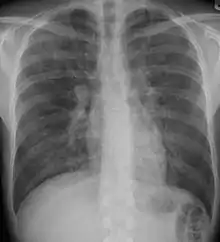

X-rays

Chest radiography is usually the first test to detect interstitial lung diseases, but the chest radiograph can be normal in up to 10% of patients, especially early in the disease process.[14][15]

High resolution CT of the chest is the preferred modality, and differs from routine CT of the chest. Conventional (regular) CT chest examines 7–10 mm slices obtained at 10 mm intervals; high resolution CT examines 1–1.5 mm slices at 10 mm intervals using a high spatial frequency reconstruction algorithm. The HRCT therefore provides approximately 10 times more resolution than the conventional CT chest, allowing the HRCT to elicit details that cannot otherwise be visualized.[14][16]

Radiologic appearance alone however is not adequate and should be interpreted in the clinical context, keeping in mind the temporal profile of the disease process.[14]